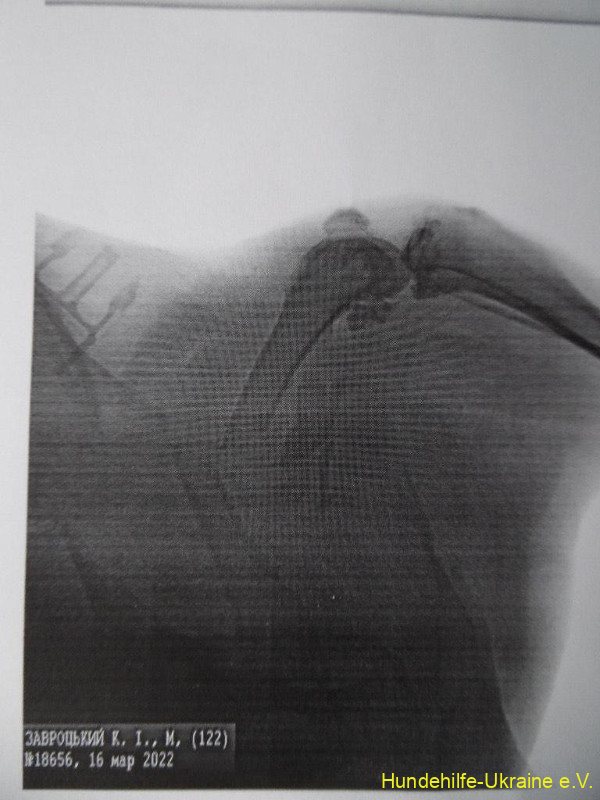

Der Hund ist sehr groß und nicht mehr jung. Sie lebt auf der Straße am Markt in unserer Stadt. Wir wurden angerufen, dass es einen Autounfall gegeben hat und dass der Hund Hilfe braucht. Wir brachten sie zum Doktor. Der Hund wurde geröntgt; ein Bein war gebrochen und es wurde operiert.

Der Hund bleibt jetzt für 3 Monate im Tierheim.